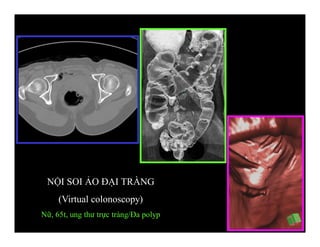

NỘI SOI ẢO ĐẠI TRÀNG

(Virtual colonoscopy)

Nữ, 65t, ung thư trực tràng/Đa polyp